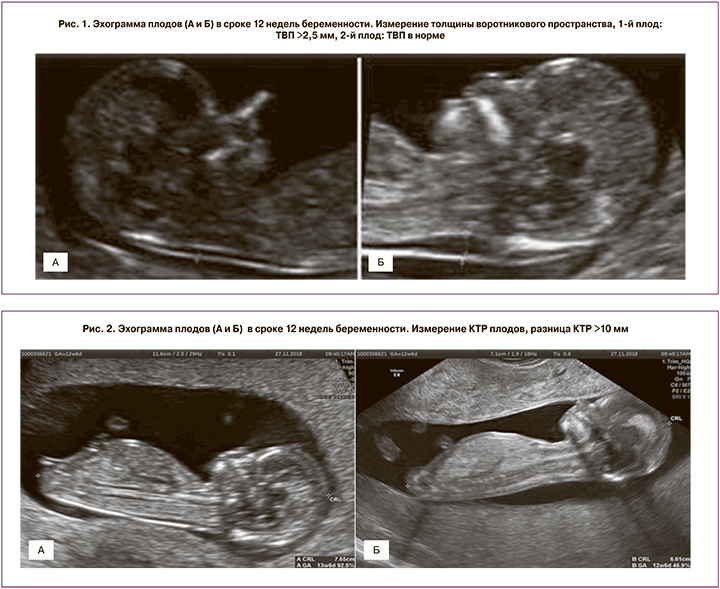

По данным ряда исследований, для прогнозирования развития специфических осложнений монохориальной беременности могут быть использованы такие эхографические параметры I триместра, как толщина воротникового пространства (ТВП) [2, 3], копчико-теменной размер (КТР) плодов [4], характер кровотока в венозном протоке [5]. Ранними проявлениями гемодинамического дисбаланса, развивающегося при ФФТС, могут быть увеличение ТВП одного плода более 95-го перцентиля и/или его дискордантность между близнецами более 0,6 мм, а также изменение кровотока в венозном протоке у одного из плодов [6]. Дискордантность КТР и окружности живота (ОЖ) плодов может являться ранним признаком ССЗРП. Несмотря на то что увеличение ТВП одного из плодов, разница в ТВП и КТР между плодами и аномальный кровоток в венозном протоке показали себя в качестве ранних признаков гемодинамического дисбаланса, возникающего при ФФТС, опубликованные данные неоднозначны. Разница ТВП плодов имеет удовлетворительную чувствительность и специфичность в прогнозировании тяжелых случаев ФФТС, однако такой скрининг до сих пор связан со значительными ложноположительными и ложноотрицательными результатами, так как частота обнаружения составляет всего 52% [7]. Также в качестве предикторов ФФТС предлагались и другие эхографические маркеры, такие как дискордантность по количеству амниотической жидкости [8], обнаружение артерио-артериальных анастомозов [9], складка межплодовой перегородки [10] и изменение уровня циркулирующей материнской м-РНК [11]. Однако их прогностическая значимость не была доказана. Таким образом, в настоящее время остается актуальным поиск ранних диагностических предикторов осложнений монохориальной беременности.

Срок беременности рассчитывался на основании КТР большего плода, измеренного в 11–14 недель беременности. Дискордантность КТР плодов выражалась в процентах и определялась по следующей формуле – разница между плодами, деленная на КТР большего плода. Значимой дискордантность считалась в случае, если она превышала 10%. Измерение ТВП плодов, кровотока в венозном протоке и других параметров скрининга I триместра проводили в сроке беременности 11–13 недель 6 дней согласно рекомендациям Международного общества ультразвуковой диагностики в акушерстве и гинекологии (ISUOG) или Фонда медицины плода (FMF). Сравнительная характеристика различных показателей эхографического исследования в I триместре беременности представлена на рис. 1–4.

При изучении роли увеличенной ТВП и ее дискордантности в качестве предиктора осложнений монохориальной многоплодной беременности было установлено, что при нормальном течении беременности монохориальной двойней, развитии ССЗРП и неразвивающейся беременности данный показатель находится в пределах нормативных значений, не превышая 95 перцентиля. Увеличение ТВП и ее дискордантности выше нормативных значений было выявлено в группе ФФТС (рис. 5).

В основе развития ФФТС лежит гемодинамический дисбаланс анастомозов плаценты между близнецами. Это приводит к перегрузке объемом сердечно-сосудистой системы одного из плодов. По данным ряда авторов, ранними проявлениями гемодинамического дисбаланса, развивающегося при ФФТС, могут быть увеличение ТВП у одного из плодов более 95-го перцентиля и/или ее дискордантность более 0,6 мм [2, 6].

Это наблюдение было также подтверждено в ходе данного исследования. По данным Sebire и соавт., было установлено, что при увеличении ТВП у одного плода более 95-го перцентиля риск развития ФФТС повышается в 4 раза [13].

В последующих работах Kagan и соавт. показали, что дискордантность ТВП более 20% (в среднем более 0,6 мм) встречается в 25% случаев монохориальной диамниотической беременности, и риск последующей ранней потери плода (до 20 недель беременности) или ФФТС был около 30% [7]. Дискордантность ТВП плодов имеет удовлетворительную чувствительность и специфичность в прогнозировании тяжелых случаев ФФТС, однако такой скрининг до сих пор связан со значительными ложноположительными и ложноотрицательными результатами, так как частота обнаружения составляет всего 52% [7].